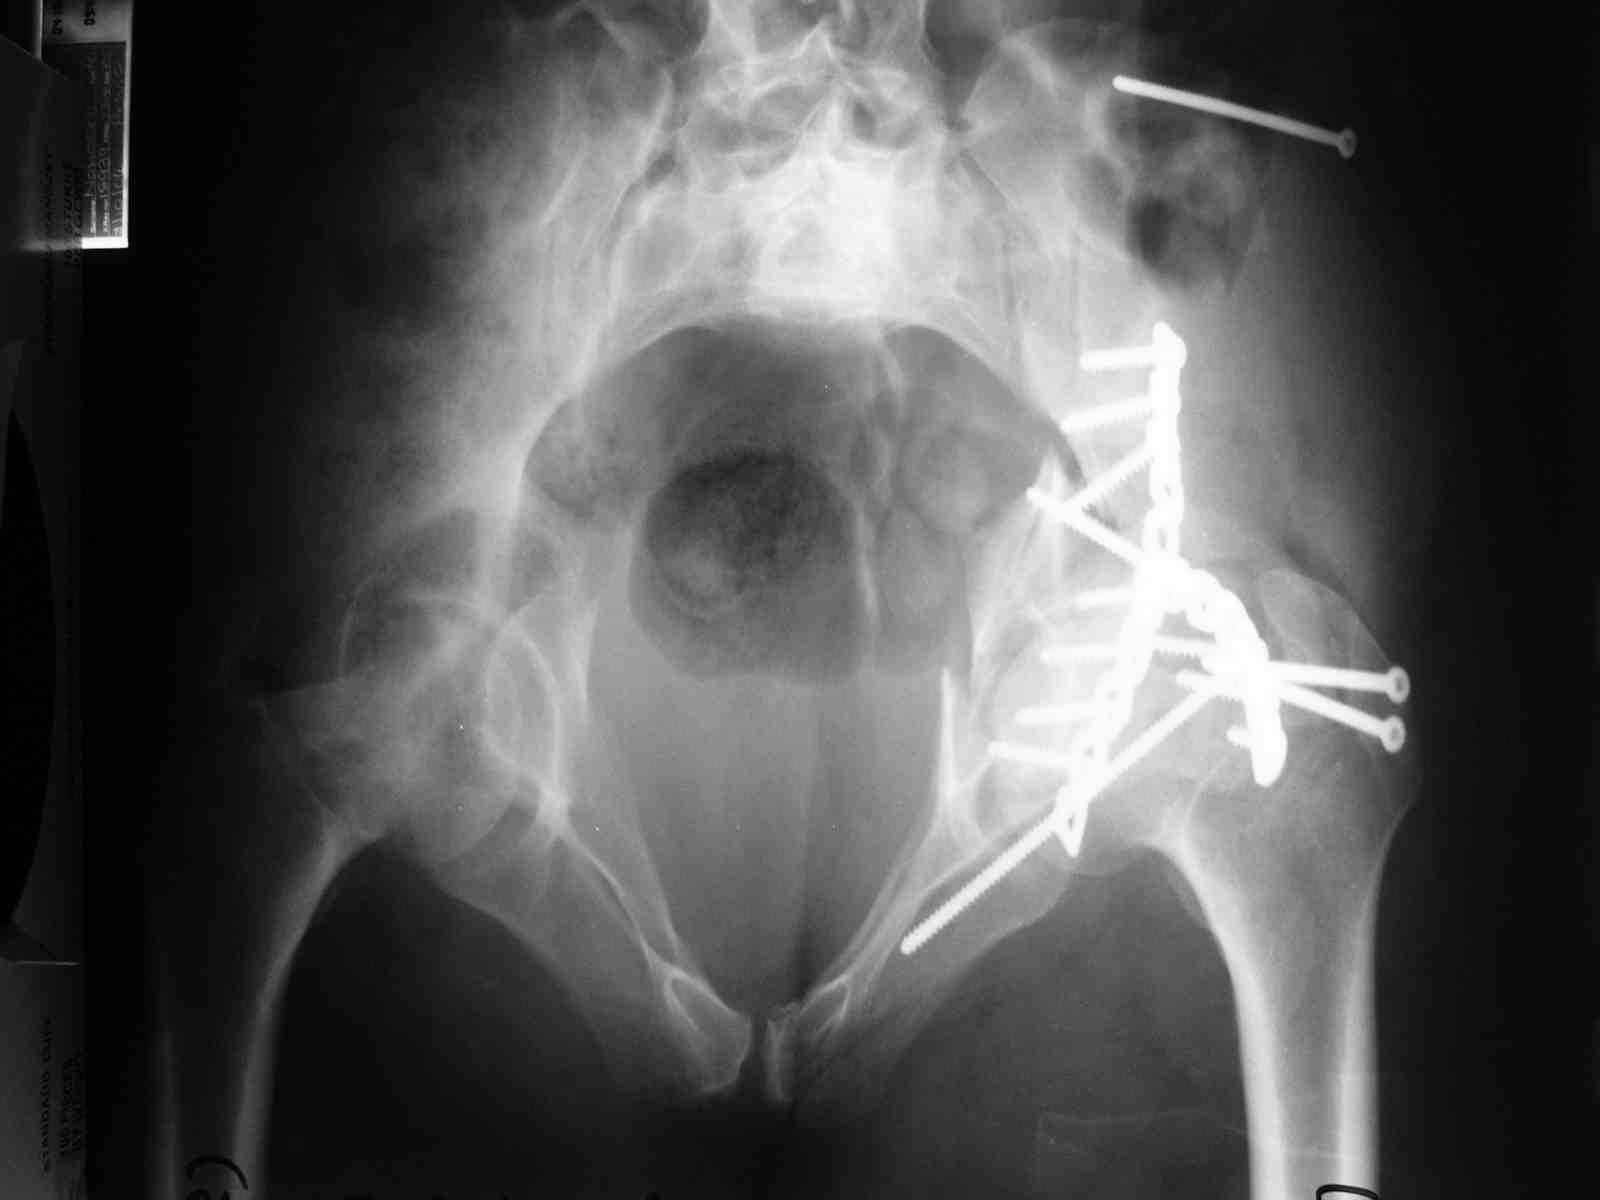

Уважаемые коллеги,43 летний мужчина, попав в автоаварию 13.10.2004, получил оскольчатый перелом обеих колонн левой вертлужной впадины.

На рентгенограммах - высокий двухколонный перелом вертлужной впадины с нарушением конгруэнтности, имеется обратная клиновидность суставной щели.

Спасибо за комментарии и рекомендации. Откровенно говоря, больного я прооперировал на прошлой неделе, через 5 дней после аварии и проблем с ним пока никаких нет, на удивление при достаточно обширной диссекции (илиофеморальный доступ) болей практически нет, так что больной самостоятельно садится в кровати, выполняет активные движения в оперированном суставе, сгибая до 60 градусов пока, далее с ассистенцией.

Причиной обращения к сообществу были возникшие непосредственно после операции сомнения и разочарования полученным качеством репозиции: а надо ли было трогать перелом вообще, репозиция передней колонны технически была очень сложна для меня, хотя реконструкции была в той же последовательности, что Д-р А.В.Рунков рекомендовал, в какой-то момент безуспешных манипуляций стал думать о *вторичной конгруэнтности*, которую не так давно обсуждали на

форуме и скелетном вытяжении. С репозицией и фиксацией задней колонны и отдельно задне-верхней стенки впадины проблем не возникло. Послеоп. Рг граммы в приложении. Если возникнут какие-либо дополнения или поправки - был бы признателен.